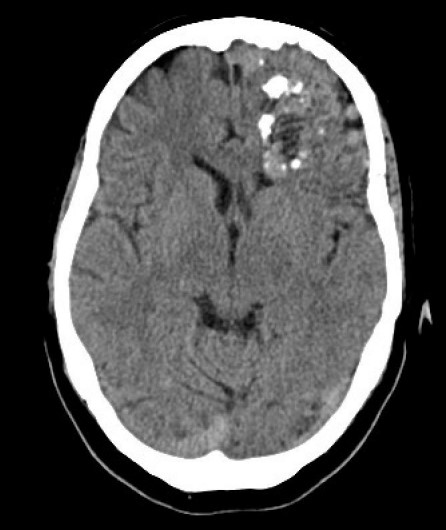

Lésions vasculaires (MAV-fistules-Moya-Moya) cérébrales et médullaires

Nerveux Vasculaire DES SPECIALITE Cerveau

• Lésions vasculaires MAV fistules Moya Moya cérébrales et médullaires